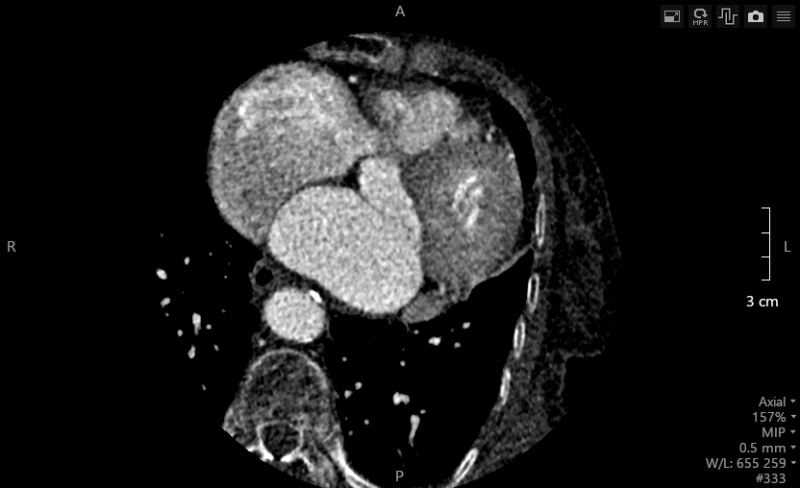

L’entraînement a duré quatre jours. Quatre-vingt-seize heures intensives à mâcher et remâcher des dizaines de milliers d’examens radiologiques venus du monde entier, à apprendre à les reconnaître. Et finalement, une aptitude incroyable à distinguer les images nécessaires des « parasites » sur les clichés. Depuis le mois de janvier 2019, l’équipe du service des urgences du CHU de Dijon travaille avec ce super assistant médical en imagerie : un scanner équipé d’une technologie de deep learning avancée. Une machine capable de voir plus de 250 niveaux de gris, quand l’œil humain n’en détaille qu’une trentaine, fournissant des radiographies d’une grande précision. « La qualité de l’image s’est significativement améliorée, constate le professeur Frédéric Ricolfi, chef du service de neuro-radiologie et de radiologie des urgences du CHU de Dijon. Les images cliniques ont moins de “bruit”, elles sont plus nettes. Les coupes sont plus fines, avec des doses de rayons X moins importantes pour les patients », poursuit le médecin.

Car c’est bien là, la problématique de tout radiologue : jusqu’à présent, pour obtenir un cliché le meilleur possible, il fallait augmenter l’exposition, à risque pour le patient. Plus les doses sont importantes, plus l’image est bonne. Un dilemme parfois pour les professionnels de santé, obligés de trouver un compromis. Surentraînée, la machine réussit à fournir un examen très précis avec une irradiation limitée, permettant aux professionnels de santé d’être plus sûrs dans le diagnostic, plus efficaces. Après trois mois d’utilisation, l’équipe du professeur Frédéric Ricolfi, au CHU de Dijon, a ainsi constaté une augmentation d’environ 25 % du rapport signal sur bruit et du rapport contraste sur bruit, synonyme d’une meilleure qualité d’image, et une diminution de la dose de rayons X de 20 % pour l’imagerie corporelle et d’environ 40 % pour les examens cardiaques.